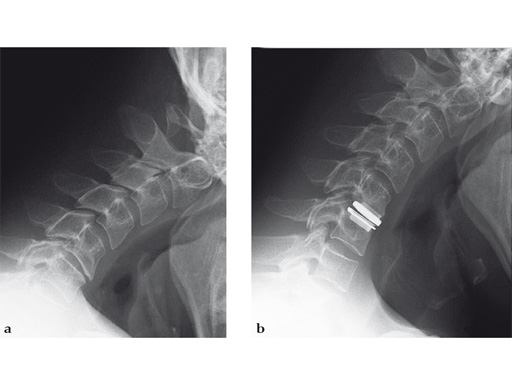

A 36-year-old man with a previous history of mild chronic neck pain developed signs and symptoms of myelopathy in four limbs after a manipulation. The MRI showed an important compressing median herniated

disc at C5/C6.

Case provided by Bonny Noens, Gent, Belgium